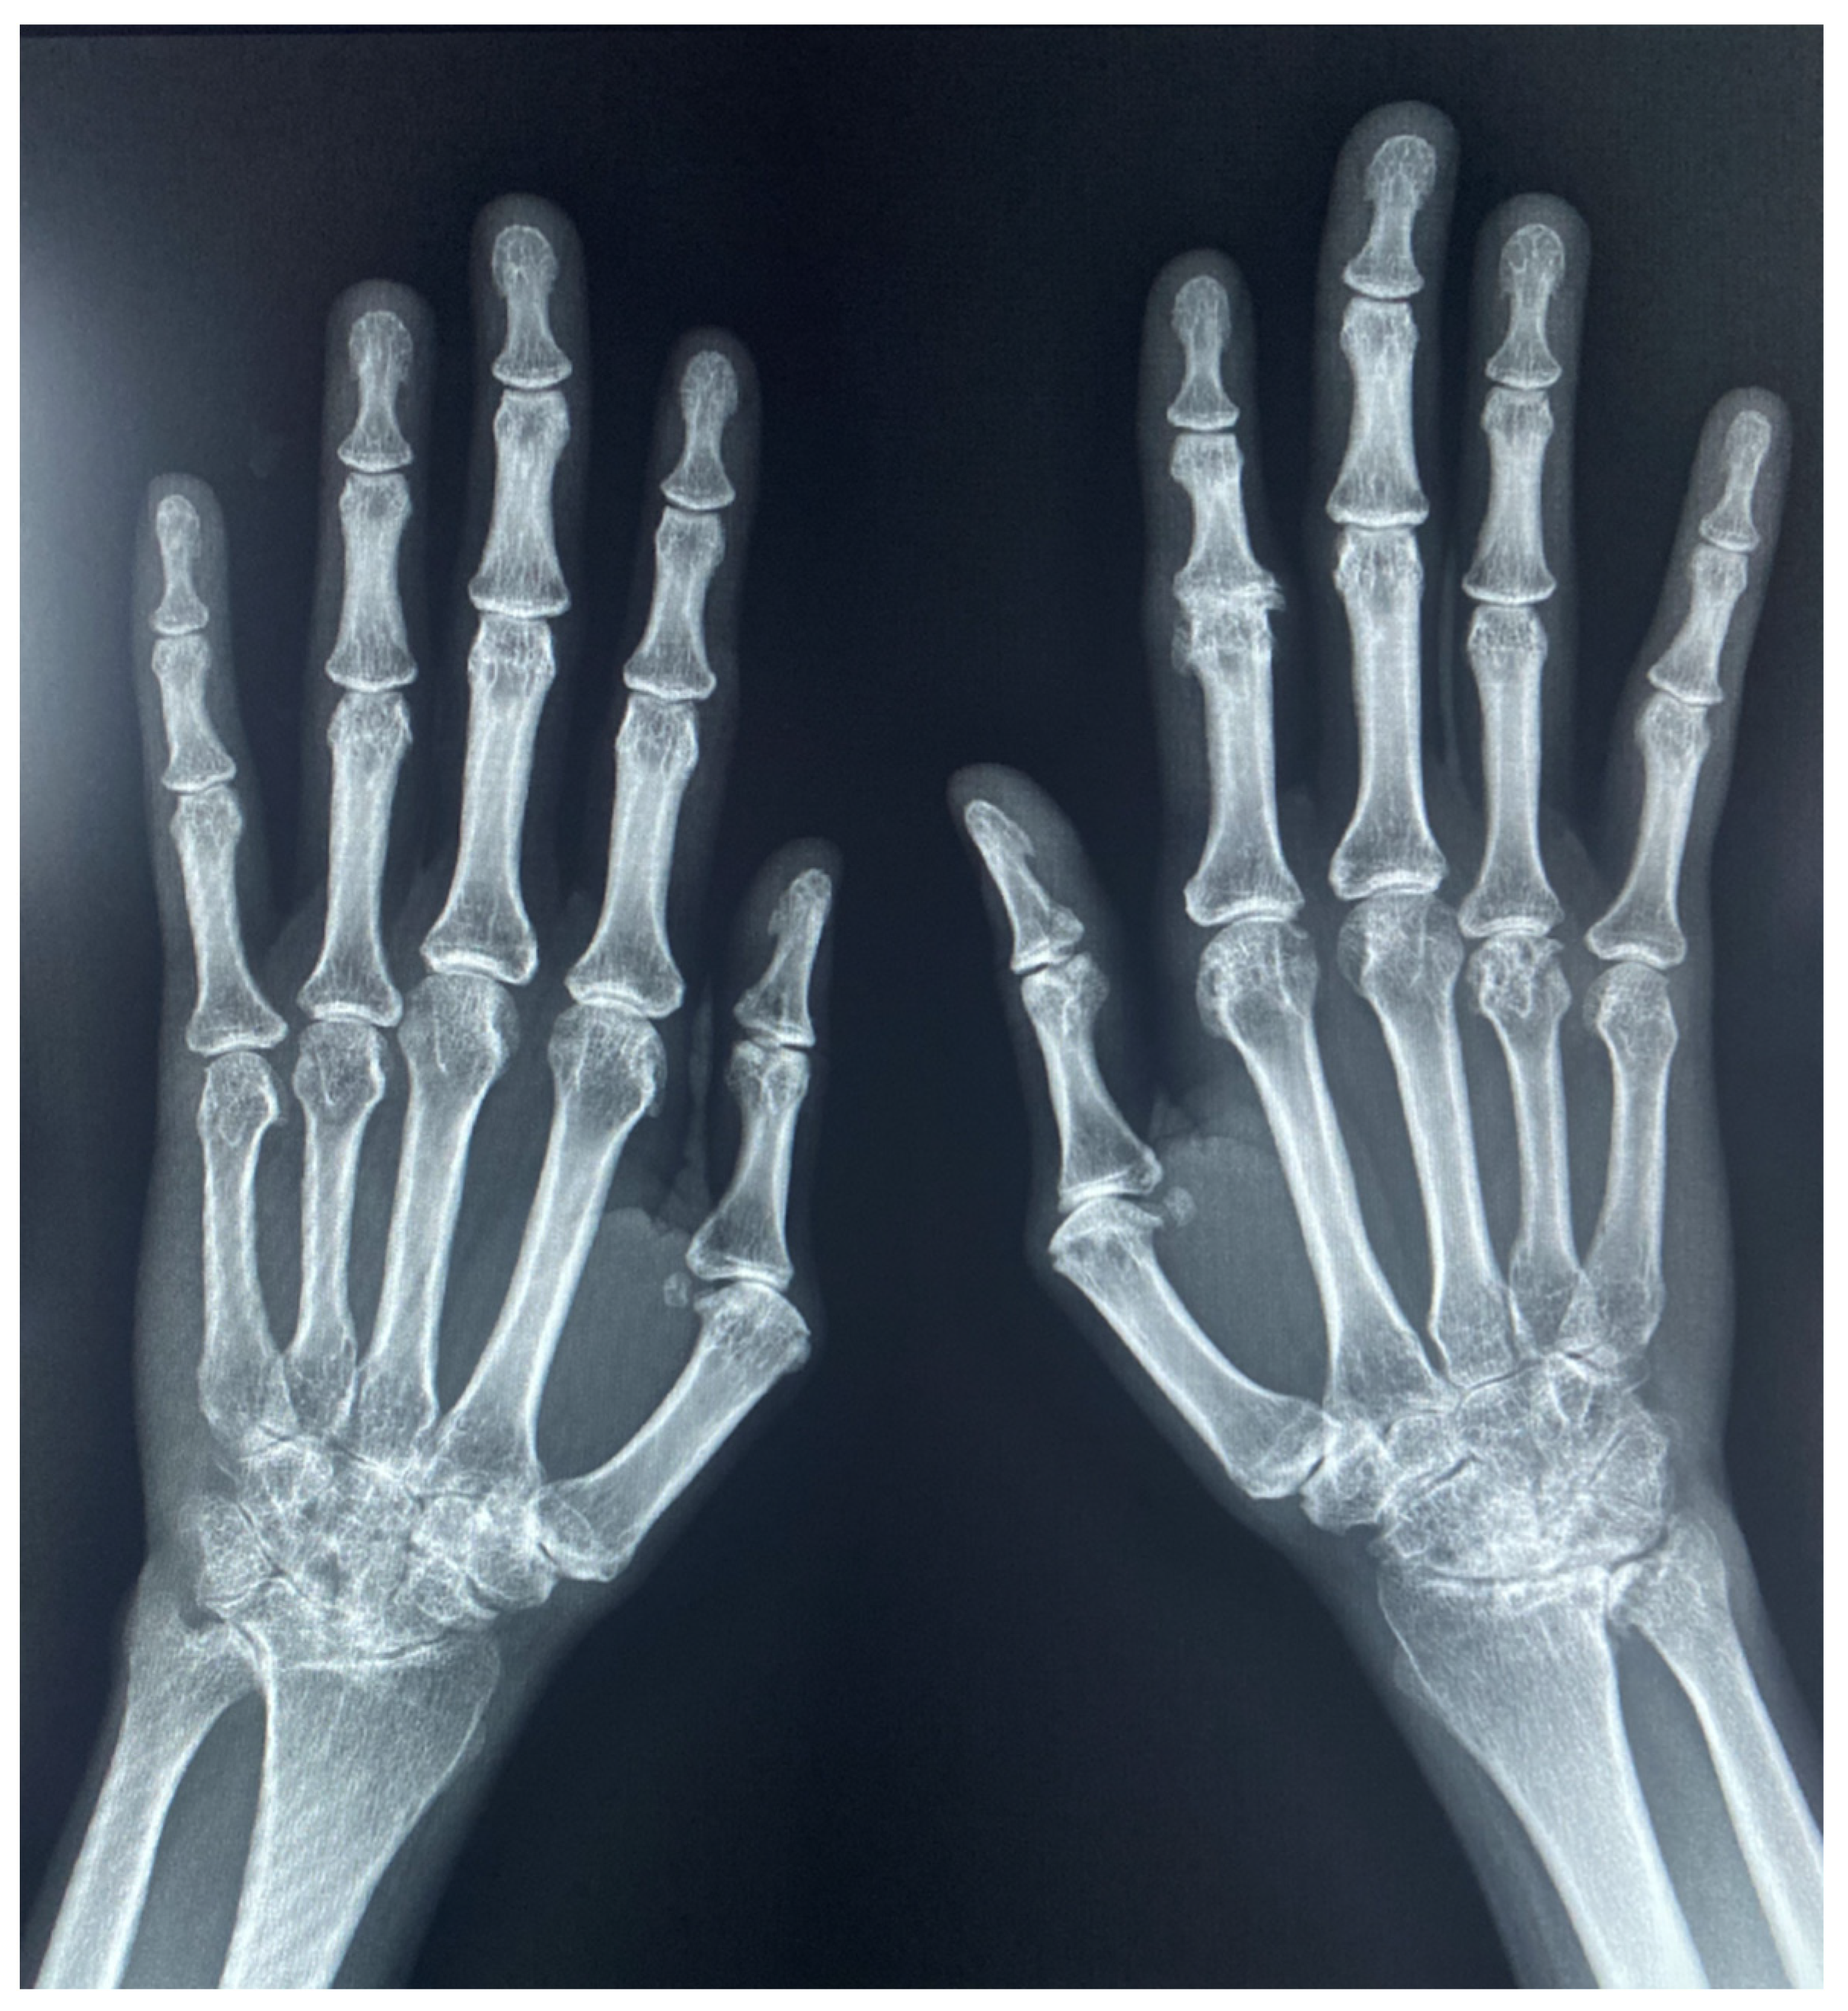

Radiographic Findings of Inflammatory Arthritis and Mimics in the Hands

3. Interpretation of the Hand Radiographs